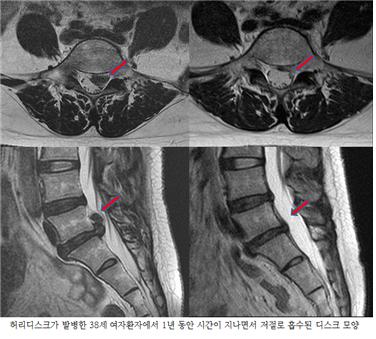

척추와 뼈 사이에 위치한 이 디스크는 외부로부터의 물리적 충격을 완화하고 단단한 뼈가 직접 충돌할 때 문제가 발생하지 않도록 하는 탄성이 높은 구조입니다. 외부의 영향이나 잘못된 위치로 인해 디스크가 꺼지면 염증이 발생하고 신경이 눌려 요통과 요통이 발생합니다. 기술적으로는 요추 디스크 분리라고 하며 일반적으로 요추 디스크 고장이라고 합니다.

디스크는 몸이 척추로부터 떨어져 많은 고통을 느낄 때까지 여러 단계를 거칩니다.